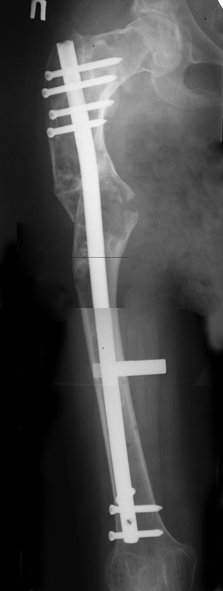

Женщина 28 лет, Больна с 12 летнего возраста, Когда после адекватной травмы получила перелом бедра. На рентгенограммах выявлено какое-то (рентгенограмм и документов нет) изменение бедренной кости, была оперирована, имеется гистологическое заключение - фиброзная дисплазия.дСформировалась деформация бедра. На сегодня - Укорочение 7см. Грубая деформация бедра по типу "пастушьей палки", последний патологический перелом в январе 2004г., консолидировавшийся при консервативном лечении. Имеются грубые изменения и в надвертлужном массиве.-- С уважением, Leonid

Возможна аппаратная коррекция оси с формированием клиновидного регенерата, которая решила бы и проблему укорочения (что, впрочем, нужно уточнить по схеме, сделанной по рентгенограмме с хорошим захватом смежных суставов - схемка по присланному снимку в приложении). По окончании коррекции - блокируемый стержень, который и сократит время пребывания в аппарате, и вообще возврата к нормальной жизни, а также будет мерой профилактики патологических переломов.

Собственно сустав не беспокоит, объем движений полный. По скиаграммам получается, что достаточно одной остеотомии на вершине деформации, чтобы восстановить длину и вывести коленный сустав в нужное положение.

Т.к. укорочение 7 см, то начинать будем с соеотомии и коррекции аппаратом. Спасибо